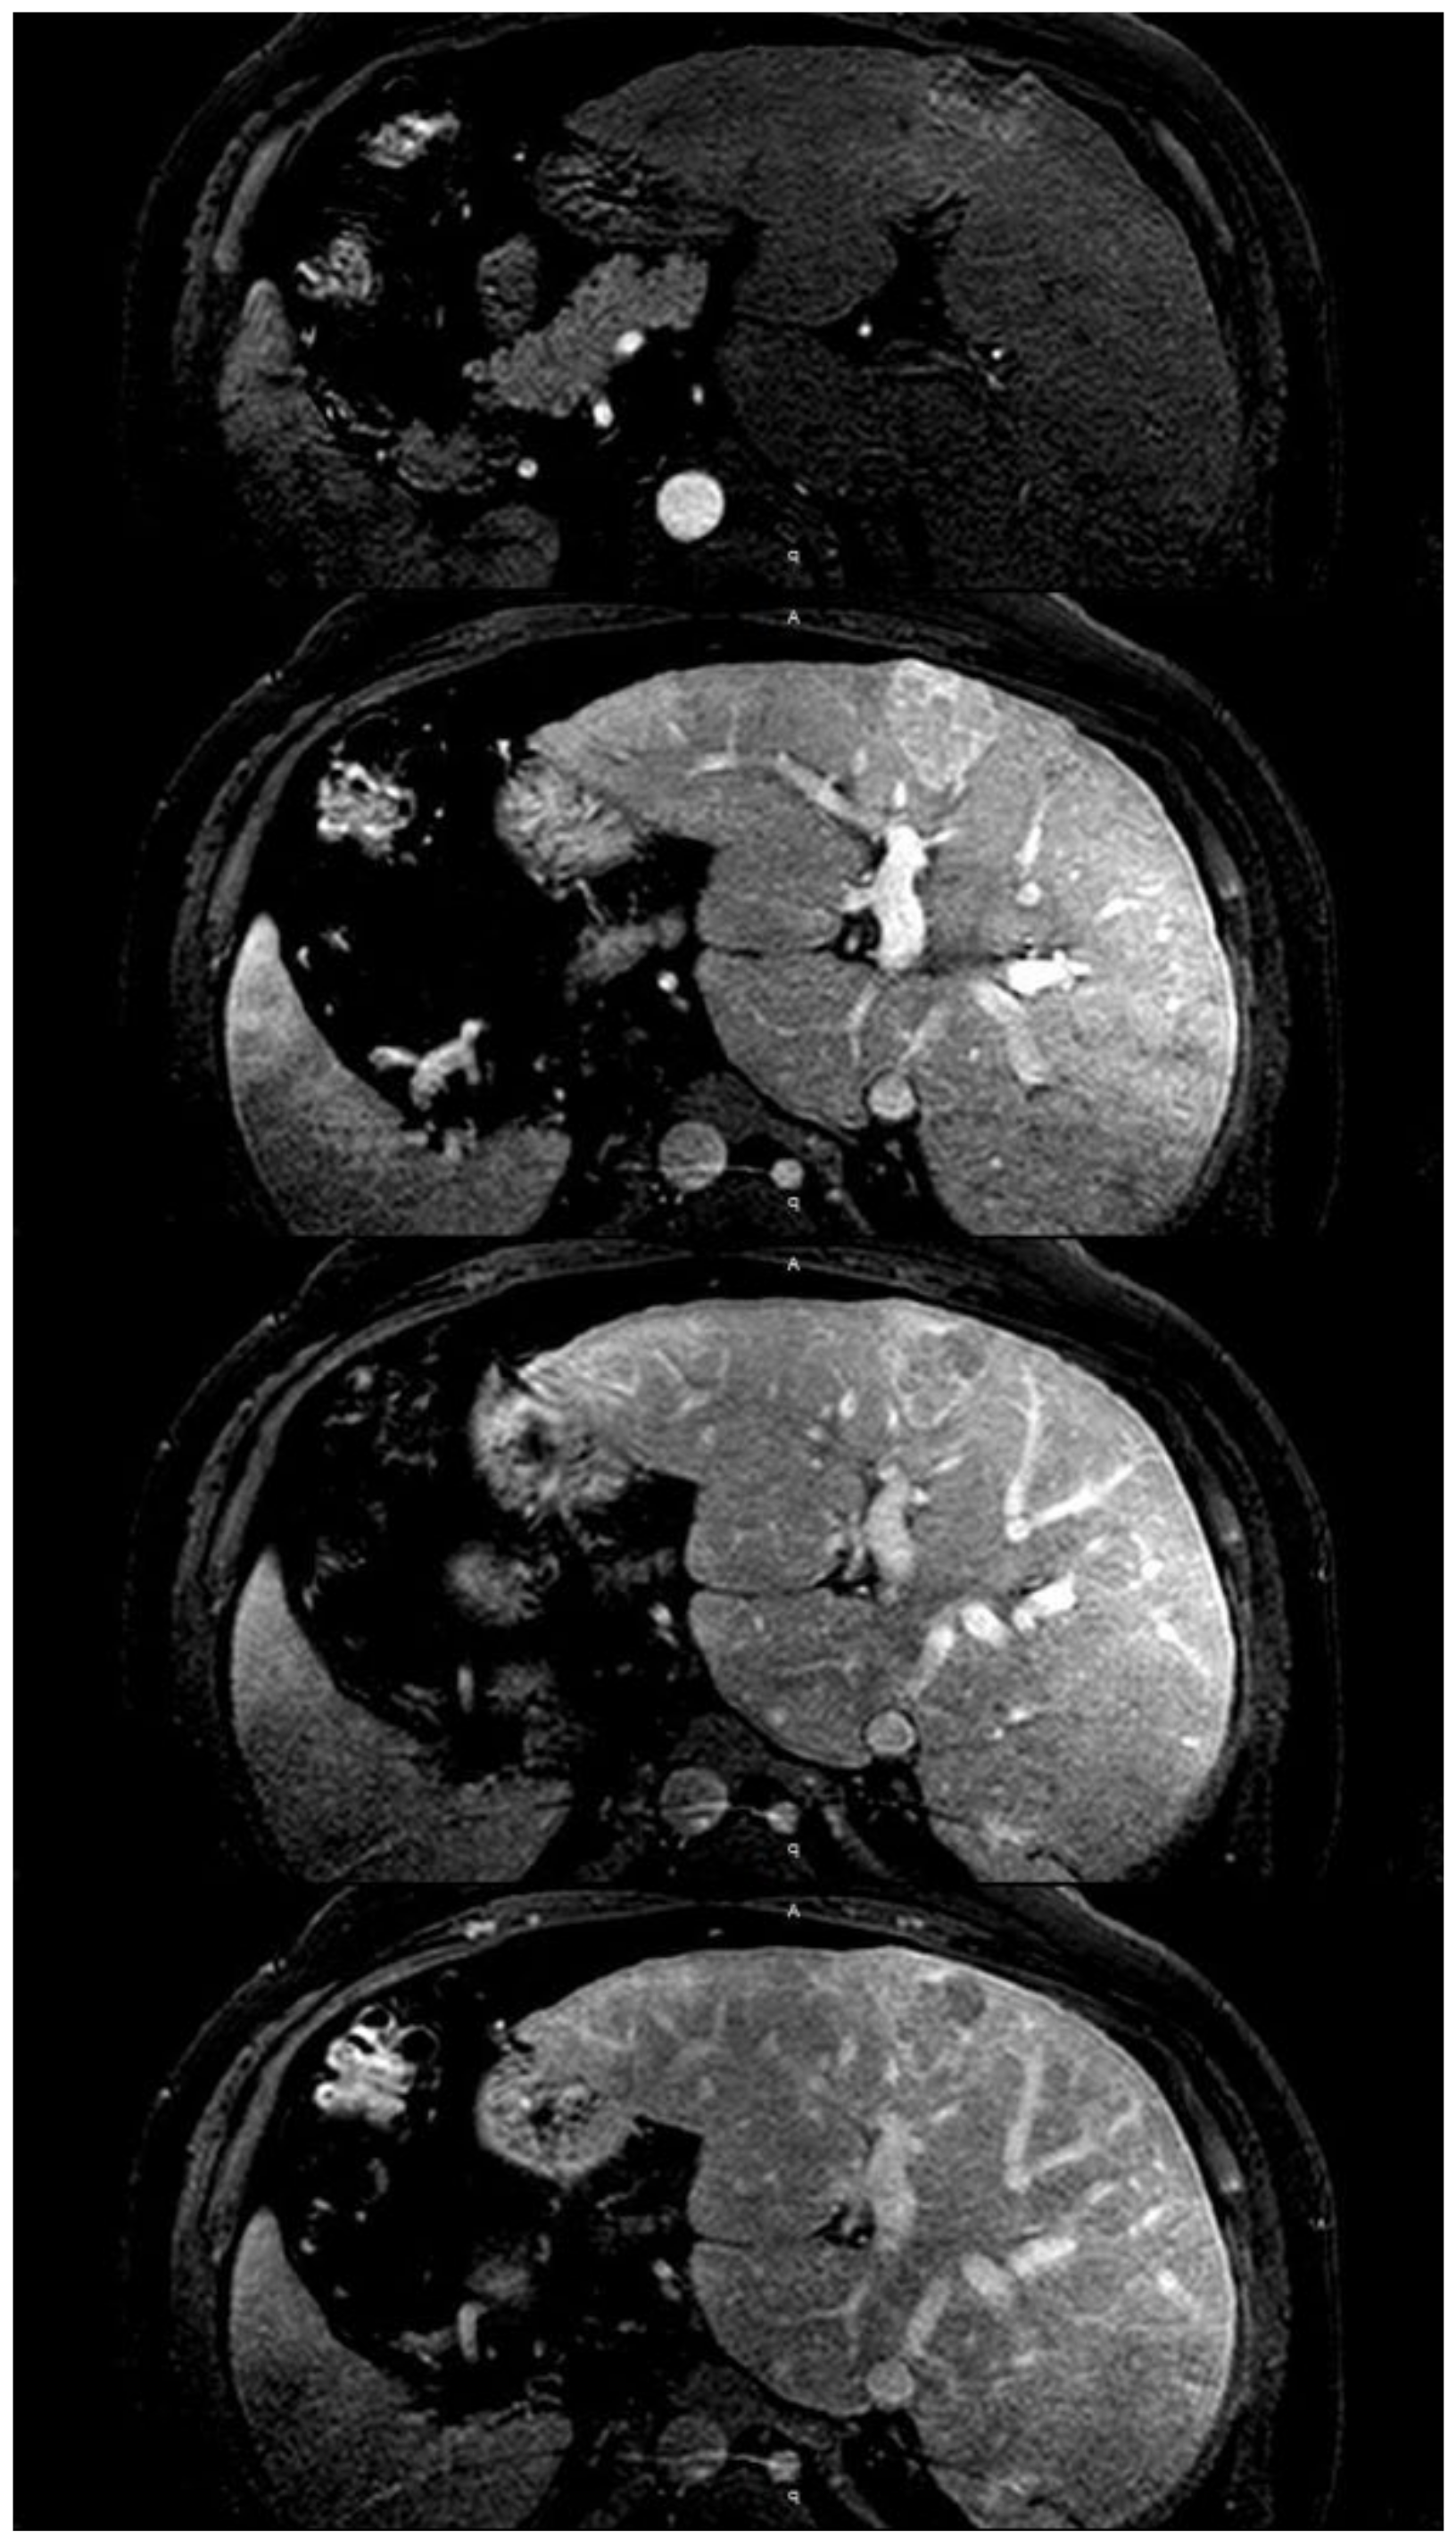

- Morales, A.; Hirsch, M.; Schneider, D.; González, D. Congestive hepatopathy: The role of the radiologist in the diagnosis. Diagn. Interv. Radiol. 2020. [Google Scholar] [CrossRef] [PubMed]

- Wells, M.L.; Venkatesh, S.K. Congestive hepatopathy. Abdom. Radiol. 2018, 43, 2037–2051. [Google Scholar] [CrossRef] [PubMed]